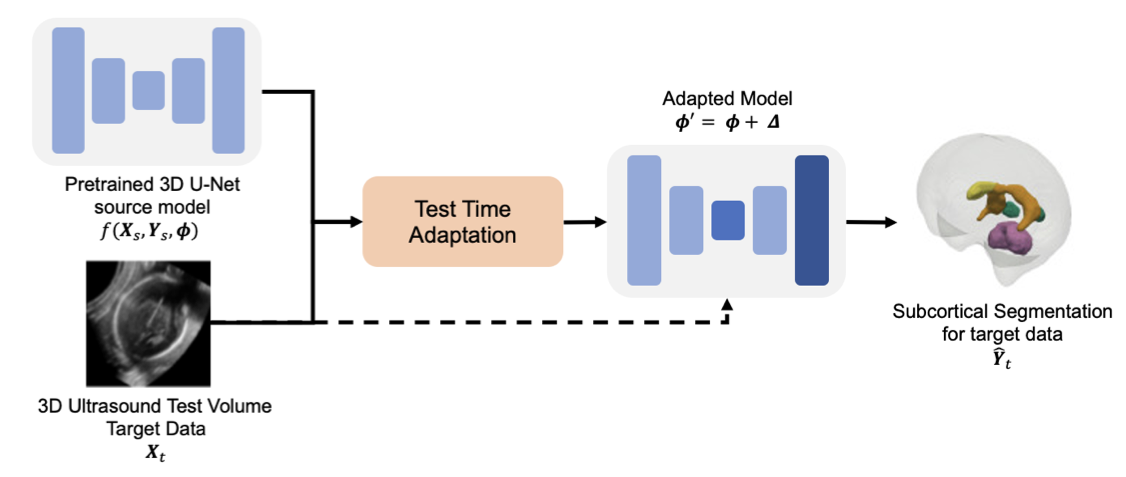

Exploring Test Time Adaptation for Subcortical Segmentation of the Fetal Brain in 3D Ultrasound

2025 IEEE 22nd International Symposium on Biomedical Imaging (ISBI)

·

14 Apr 2025

·

doi:10.1109/ISBI60581.2025.10980676